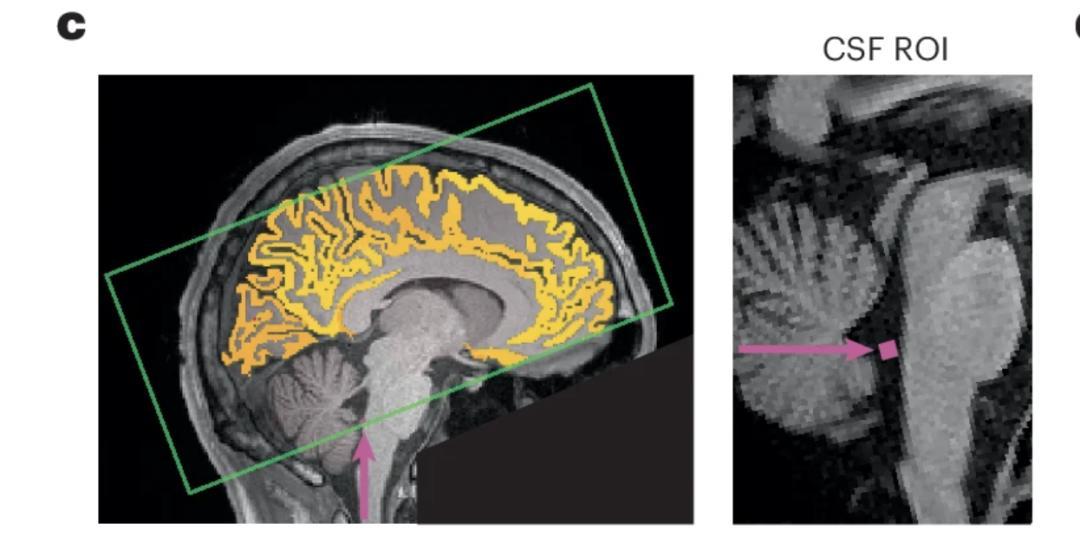

2025 年 10 月發表在《自然神經科學》雜誌上的一篇研究指出,熬夜後的注意力不集中,可能是因爲你的大腦正在給自己「洗澡」[1]

腦科學界這幾年有個新理論:大腦會在白天產生代謝廢物,在睡眠時通過腦脊液不斷沖刷、清除掉,從而讓大腦再次恢復清潔。[1][2]

研究人員找來了 26 位成年人,讓他們在一次實驗中睡得很好,另一次則整晚不睡。不出意外,熬夜的那次,簡單的注意力測試表現很差。

有趣的是,通過腦部 MRI 掃描發現:

每次注意力「斷片」的前 2 秒,腦脊液會被衝出腦底;而注意力恢復後的 1 秒,又會被重新吸回大腦。

也就是說,你在發呆、走神的時候,大腦正在進行「緊急衝洗」。

研究者形容:「這就像洗衣機——先加水,再攪動、再排水。注意力走神時,大腦正好在『攪』。」